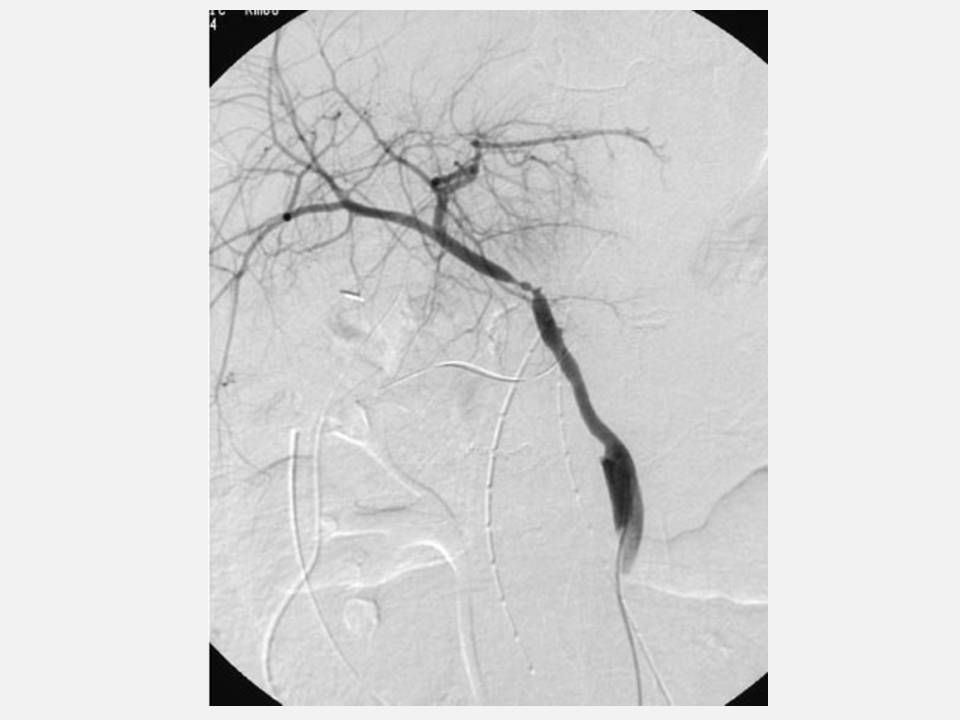

From radiologykey.com

Liver Transplantation Imaging Radiology Key Arterial Conduit Liver Transplant arterial conduits (ac) in liver transplantation (lt) offer an effective rescue option when regular arterial graft revascularization is not feasible. Arterial conduits (ac) in liver transplantation (lt) offer an effective rescue option when regular. Arterial conduits (ac) in liver transplantation (lt) offer an effective rescue option when regular arterial graft revascularization is not. although aortohepatic conduits (ahcs) provide. Arterial Conduit Liver Transplant.